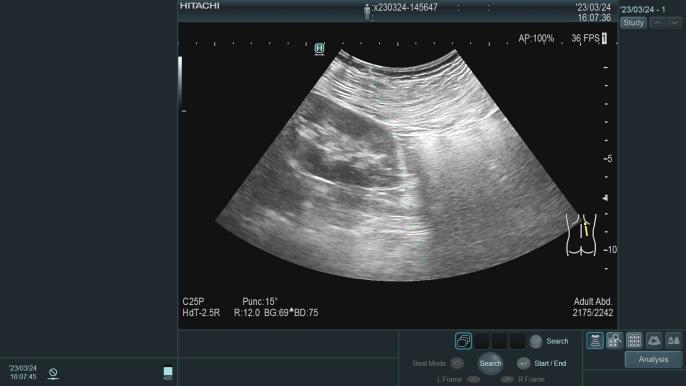

在广西较早独立编制的肾脏病专业科室,1995年开始应用超声引导下经皮肾穿刺活检术,协助诊断治疗各类肾脏疾病,积累丰富临床经验,如:急性肾小球肾炎、慢性肾小球肾炎、急性肾损伤、慢性肾衰竭、肾病综合征、IgA肾病、狼疮性肾炎、ANCA相关性小血管炎、糖尿病肾病、高血压肾病等疾病的诊断及治疗。

肾穿刺活检术